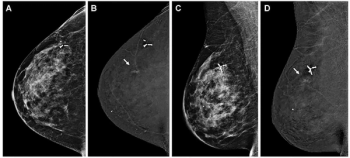

In a study involving over 24,000 women, two-thirds of whom had dense breasts, adjunctive AI led to a significantly higher rate of cancer detection for breast radiologists with no difference in recall rates.

In a recent interview, Emily Conant, M.D., discussed findings from two studies presented at the European Congress of Radiology (ECR) conference that showed the potential impact of image-based AI risk models and breast arterial calcification detection in mammography screening.